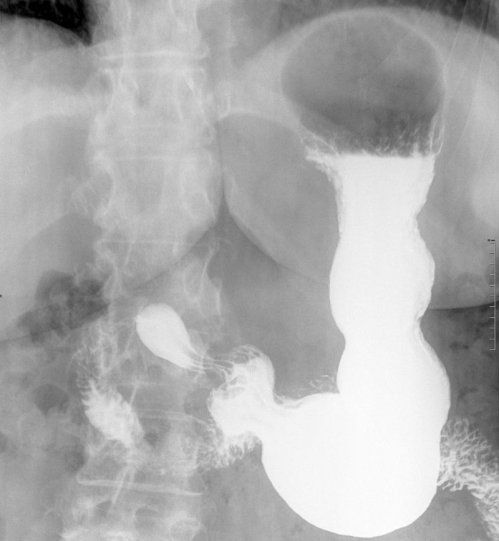

Estudios EGD y tránsito intestinal

El estudio EGD y tránsito intestinal es un estudio con Rayos X del esófago, estómago y duodeno, sí se extiende a todo el intestino delgado se denomina tránsito intestinal completo. Es necesario beber un liquido de bario, con normalmente sabor a fresa o vainilla para ver las estructurasdigestivas con Rayos X.

El estudio gastroduodenal (EGD) y tránsito intestinal se realiza para valorar la forma y la función de las estructuras digestivas, con mayor frecuencia se utiliza para valorar reflujo en pacientes con dolor, se pueden detectar úlceras, tumores o inflamación.

Durante la exploración se ve el paso del bario a lo largo del tubo digestivo y mientras tanto se van obteniendo radiografía. La exploración tiene una duración aproximada de 20 minutos; si se realiza tránsito intestinal se prolongará hasta dos horas más, este es un tiempo aproximado que puede variar en cada paciente y en relación con la rapidez con que pase el bario por el intestino.